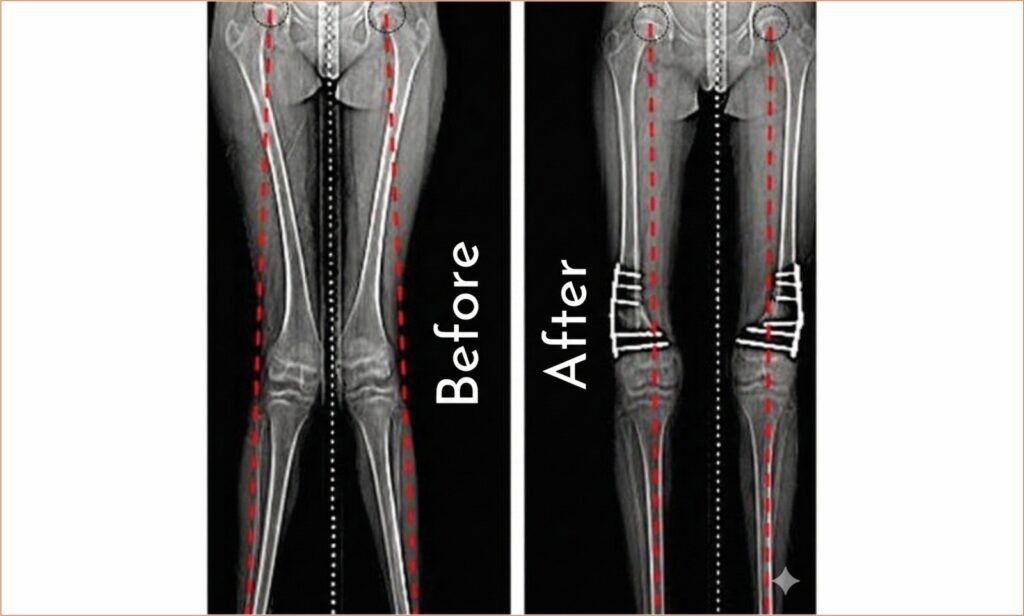

Patient Profile Age: 8 years Gender: Female Location: Jhunjhunu, Rajasthan Presenting ComplaintAn 8-year-old girl presented with a bent knee deformity